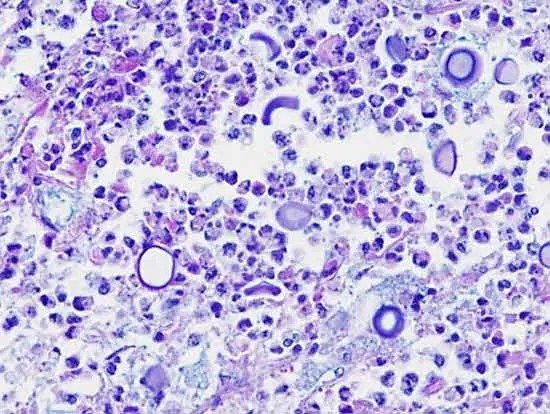

Cryptococcus is a type of fungus that is gaining attention worldwide due to its impact on human health. This genus of fungi includes species that can cause serious infections, especially in people with weakened immune systems. The most well-known species are Cryptococcus neoformans and Cryptococcus gattii. These fungi are encapsulated yeasts, meaning they have a thick outer layer called a capsule. This capsule helps the fungus survive in tough conditions and avoid being destroyed by the body’s immune defenses.

The infection caused by Cryptococcus is called cryptococcosis. It mainly affects the lungs and the central nervous system, including the brain and spinal cord. When the fungus infects the lungs, it can cause symptoms like cough, chest pain, fever, and difficulty breathing. This lung infection can be mild or severe depending on how strong the person’s immune system is. The more dangerous form of the disease occurs when the fungus spreads to the brain, causing cryptococcal meningitis. This condition leads to inflammation of the membranes surrounding the brain and spinal cord. Symptoms of meningitis include headaches, fever, stiff neck, confusion, and can be life-threatening if not treated quickly.

To diagnose cryptococcosis, doctors look for the presence of the fungus or its antigens in blood, spinal fluid, or tissue samples. Imaging tests like chest X-rays or CT scans can help detect infections in the lungs or brain. Treatment usually involves antifungal medications such as amphotericin B, flucytosine, and fluconazole. These drugs can be very effective, but treatment often needs to be long and closely monitored, especially when the infection involves the brain.